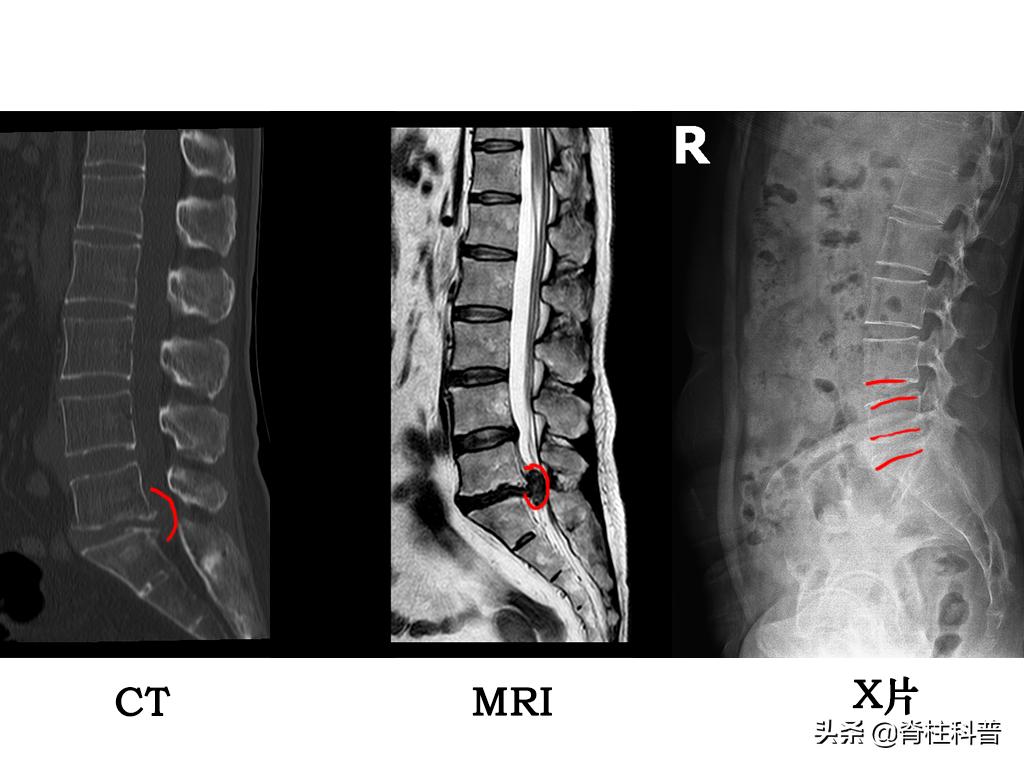

在解释上述问题的之前,我们先来直观的看一下MRI、CT、X线的图片。我找了一位发病经过最常见、求诊片子最凸显的病人做案例。来我科做手术的腰椎间盘突出症的患者多数为40-60岁年龄段(符合该病的发病年龄段)。

45岁女性患者,因“反复腰痛并左下肢疼痛3年余,再发并加重10余天”前来就诊的。

患者3年多以前,在无明显诱因的情况下出现腰痛,左下肢疼痛,以左大腿后侧明显,劳累时明显,久站久坐后加剧,休息后可以缓解。接受按摩等保守治疗(具体情况不详),效果一般。此后,上述症状反复发作。10多天以前,搬抬重物后再发并较前加重,伴有间歇性跛行。就诊于外院,接受腰椎间盘微创治疗(具体术式不详),疗效差。术后腰痛、左下肢疼痛未见明显缓解。近日,症状加重,出现左臀部疼痛、麻木,大便困难。为求进一步的治疗,前来我院。

图片源自:南方医科大学第三附属医院脊柱外科

椎间盘突出的程度不同,脊髓、神经受压的情况不同,患者表现出来的症状不同,在临床治疗上会根据病情采用不同的方法,所以需要经过影像学进行鉴别诊断,以便更有效的实施治疗。